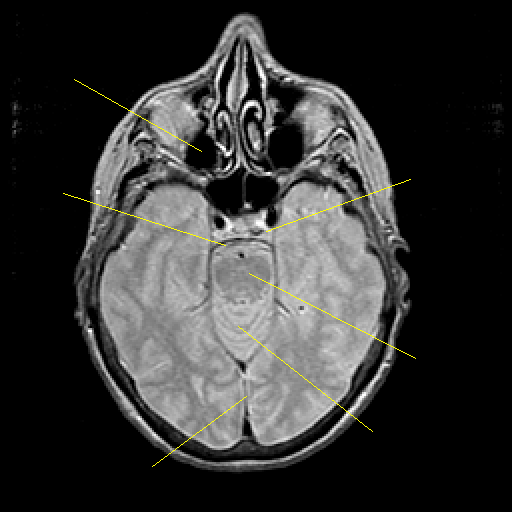

Proton density-weighted structural MR: Slice 19

Slice 19

Pointers

Labeled